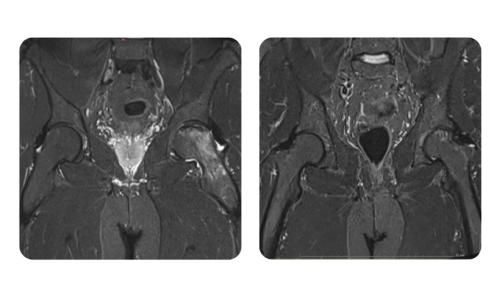

I progressi dei nostri pazienti, misurati prima e dopo la terapia iperbarica, riflettono l'efficacia e l'impatto positivo del trattamento. Scopri i risultati documentati della terapia iperbarica presso la clinica Hyperbarium Oradea, basati su valutazioni cliniche e dati oggettivi che evidenziano miglioramenti significativi in diverse condizioni.